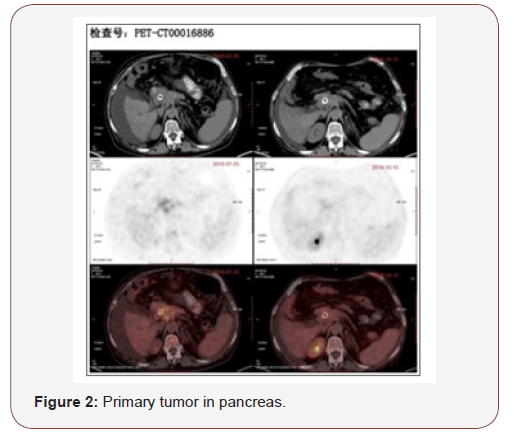

A review of PET/CT (Oct 15, 2018) compared with July 23, 2018 before treatment.

B. Multiple lymph nodes around pancreas and retroperitoneal region, multiple metastatic tumor in liver, metabolism reduced compared with the former scan. Considered suppressed of activity after treatment (Figure 2).